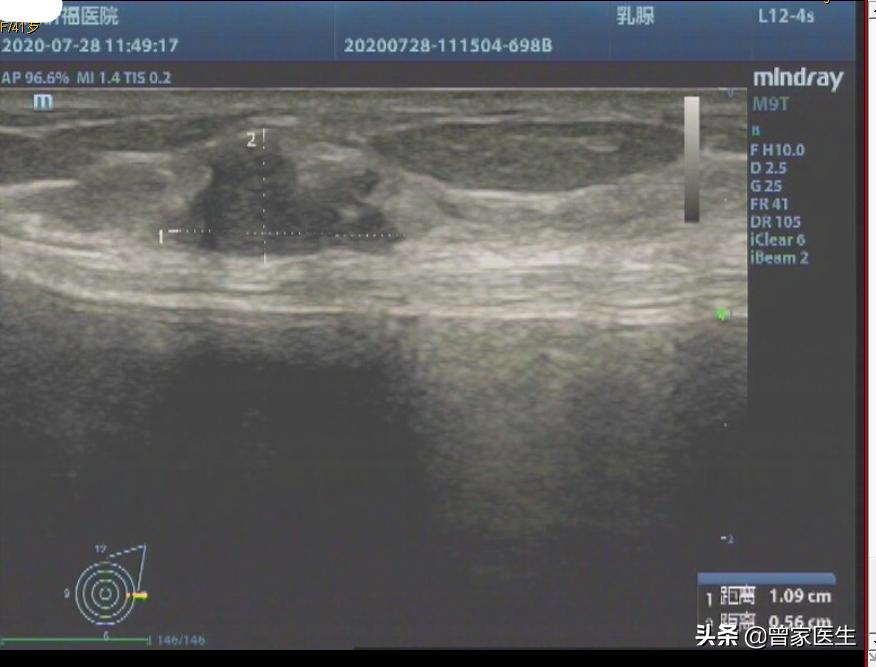

刚进来的时候,患者表现很镇静,我看了她的彩超报告,详细看看彩超里面的图片,感觉有点像恶性肿瘤。大家看看下面图片。

彩超里面的描述

形态不规则